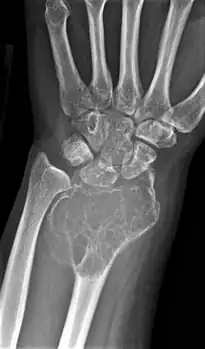

On X-ray, giant-cell tumors (GCTs) are lytic/lucent lesions that have an epiphyseal location and grow to the articular surface of the involved bone.[11] Radiologically the tumors may show characteristic 'soap bubble' appearance.[12] They are distinguishable from other bony tumors in that GCTs usually have a nonsclerotic and sharply defined border. About 5% of giant-cell tumors metastasize, usually to a lung, which may be benign metastasis,[13] when the diagnosis of giant-cell tumor is suspected, a chest X-ray or computed tomography may be needed. MRI can be used to assess intramedullary and soft tissue extension.